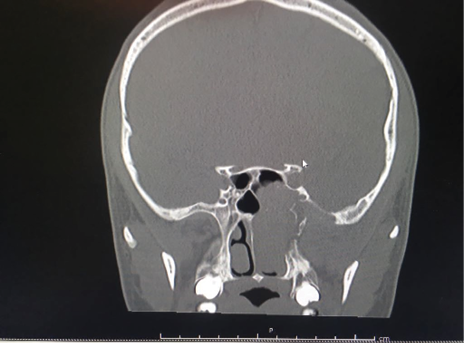

El corte coronal observamos masa en fosa nasal izquierda con compromiso del suelo de la celda esfenoidal izquierda. (Figura 2).